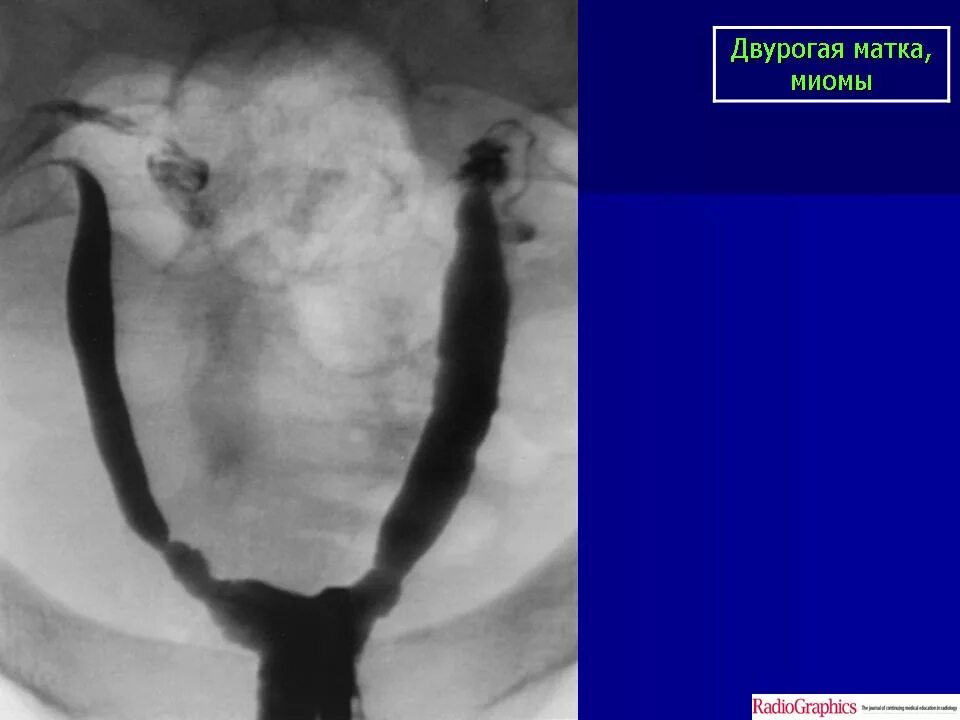

Что такое две матки у женщины